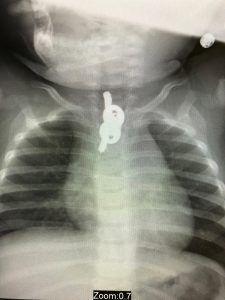

ההפתעה שציפתה להורים הייתה גדולה מאוד. בצילום נראו זוג מפתחות בוושט בגובה החזה. התינוק הובהל מידית למרכז הרפואי שערי צדק ושם כאמור הוצאו המפתחות ללא נזק.

במהלך ראש השנה הובא למיון ילדים בשערי צדק תינוק כבן 10 חודשים, לאחר שבצילום רנטגן שבוצע במרפאת טרם התברר שבלע זוג מפתחות.